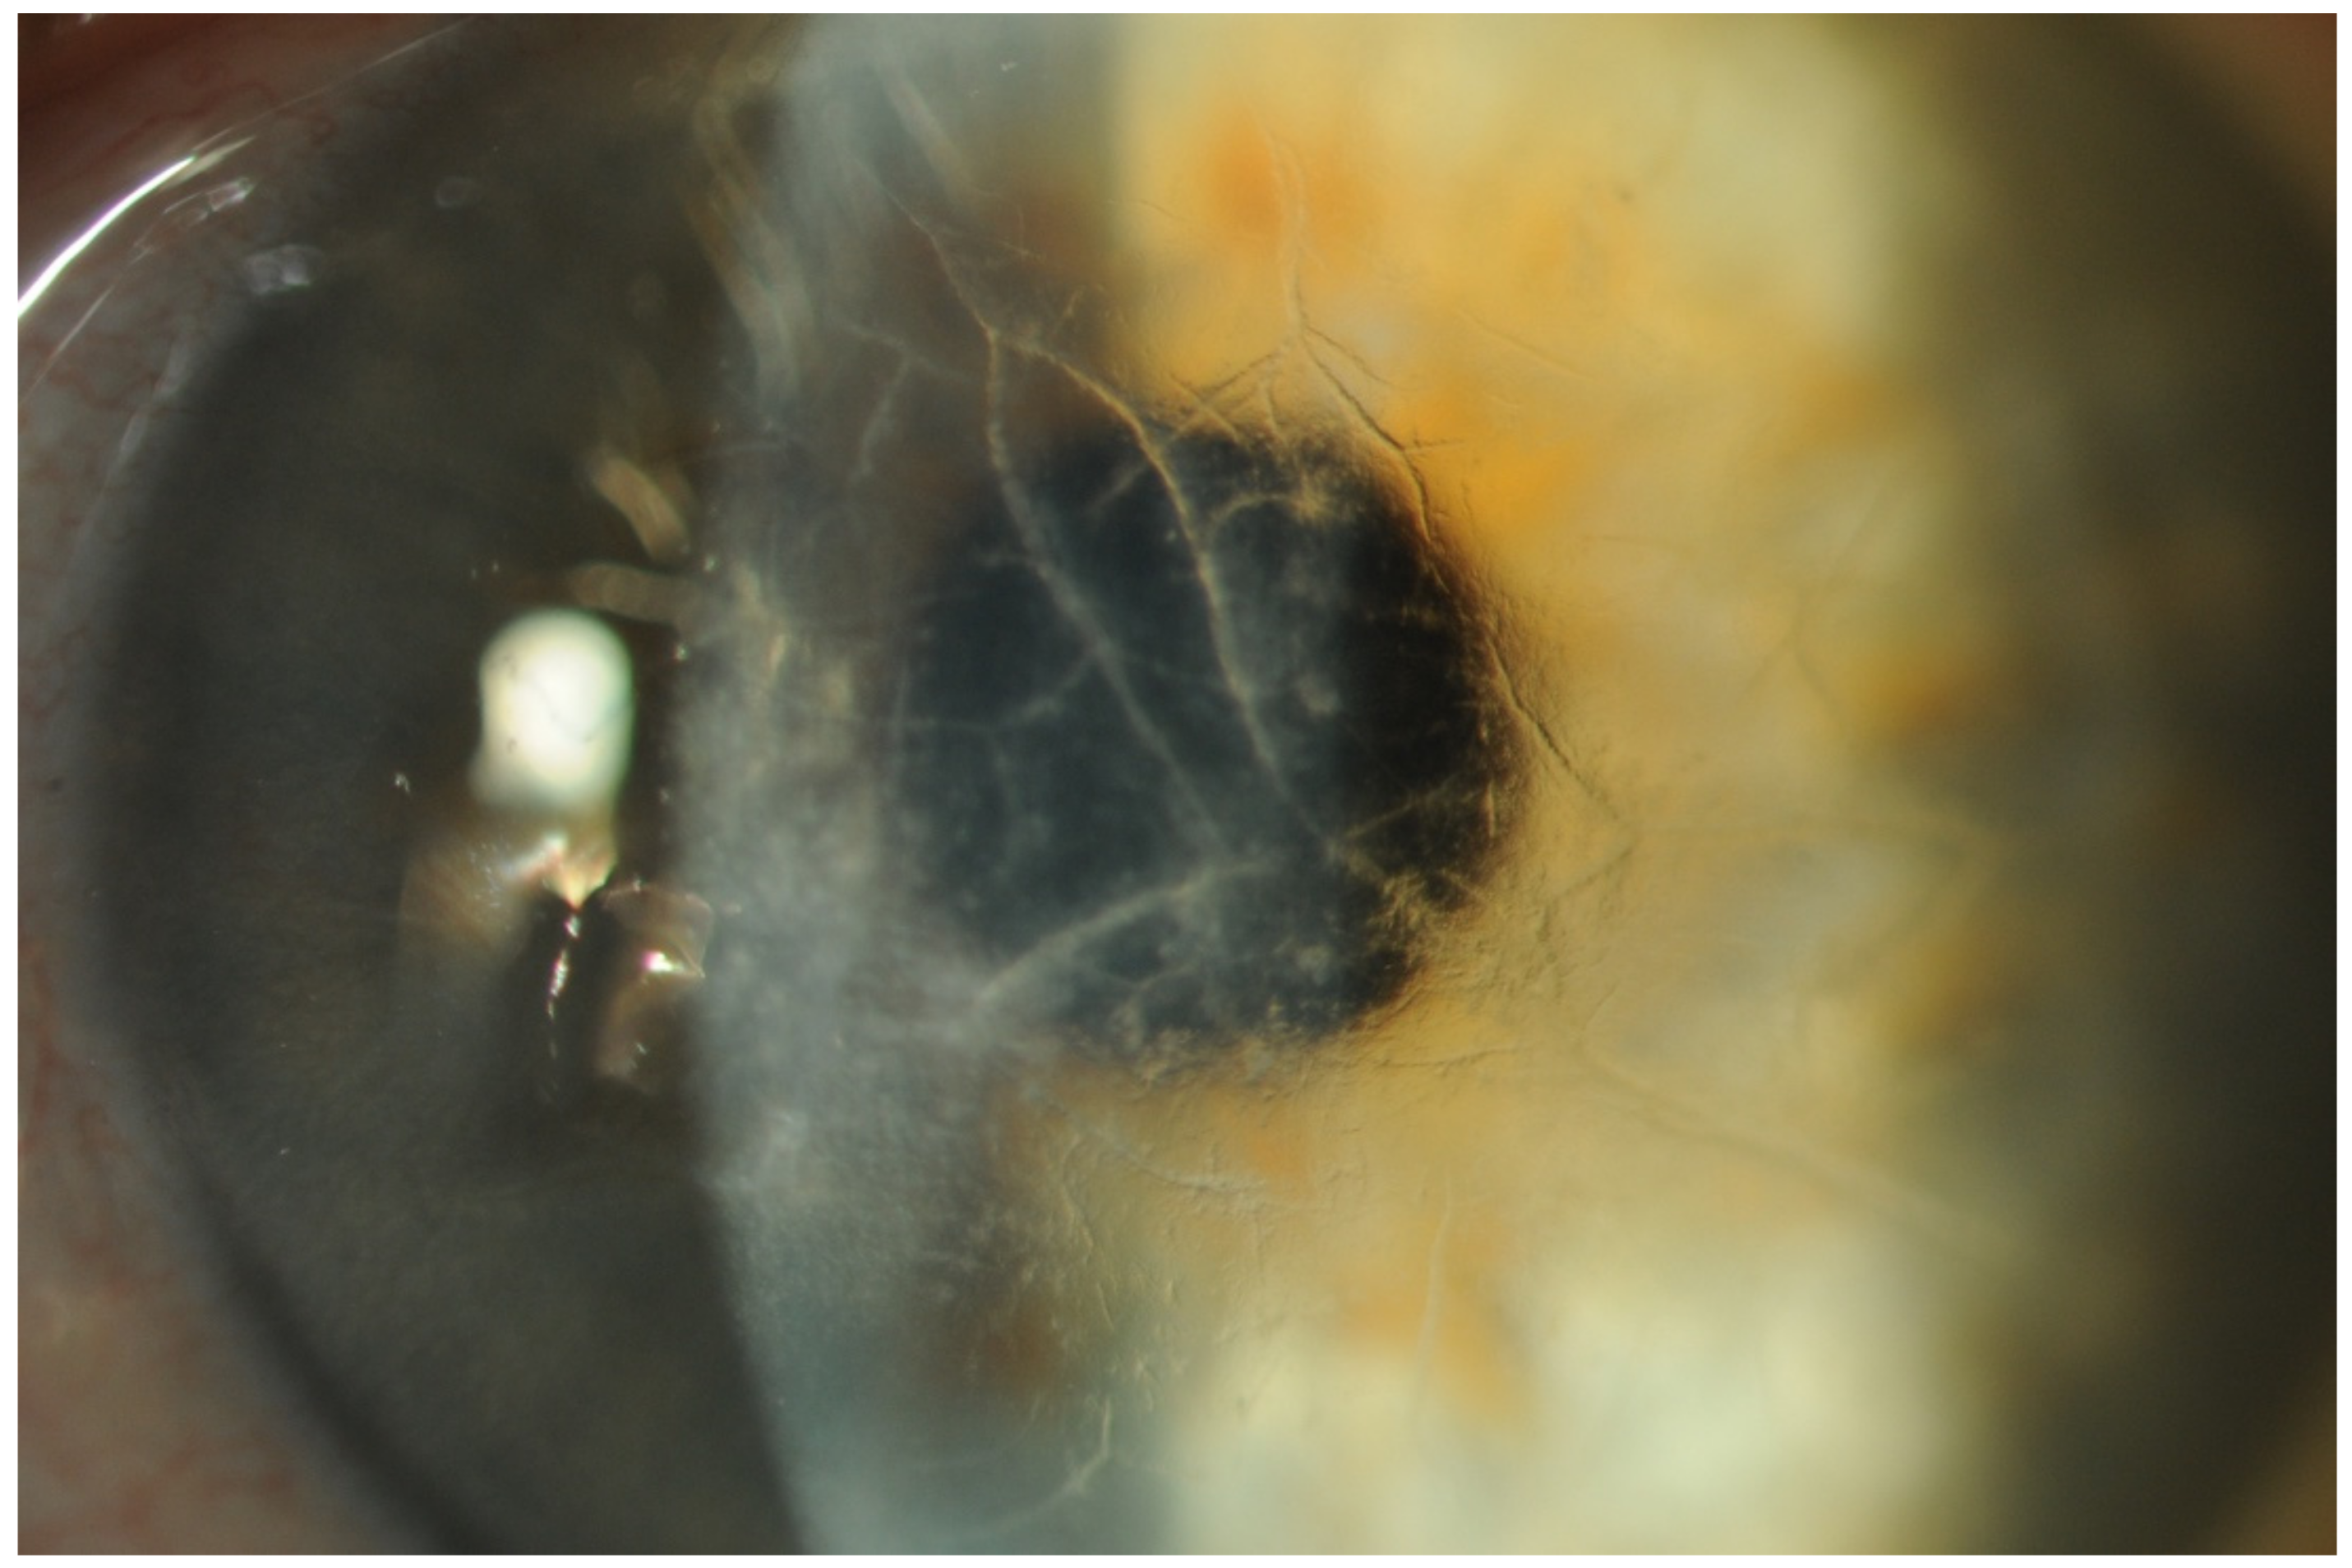

- Abnormal Conjunctival Vessels (ACVs)